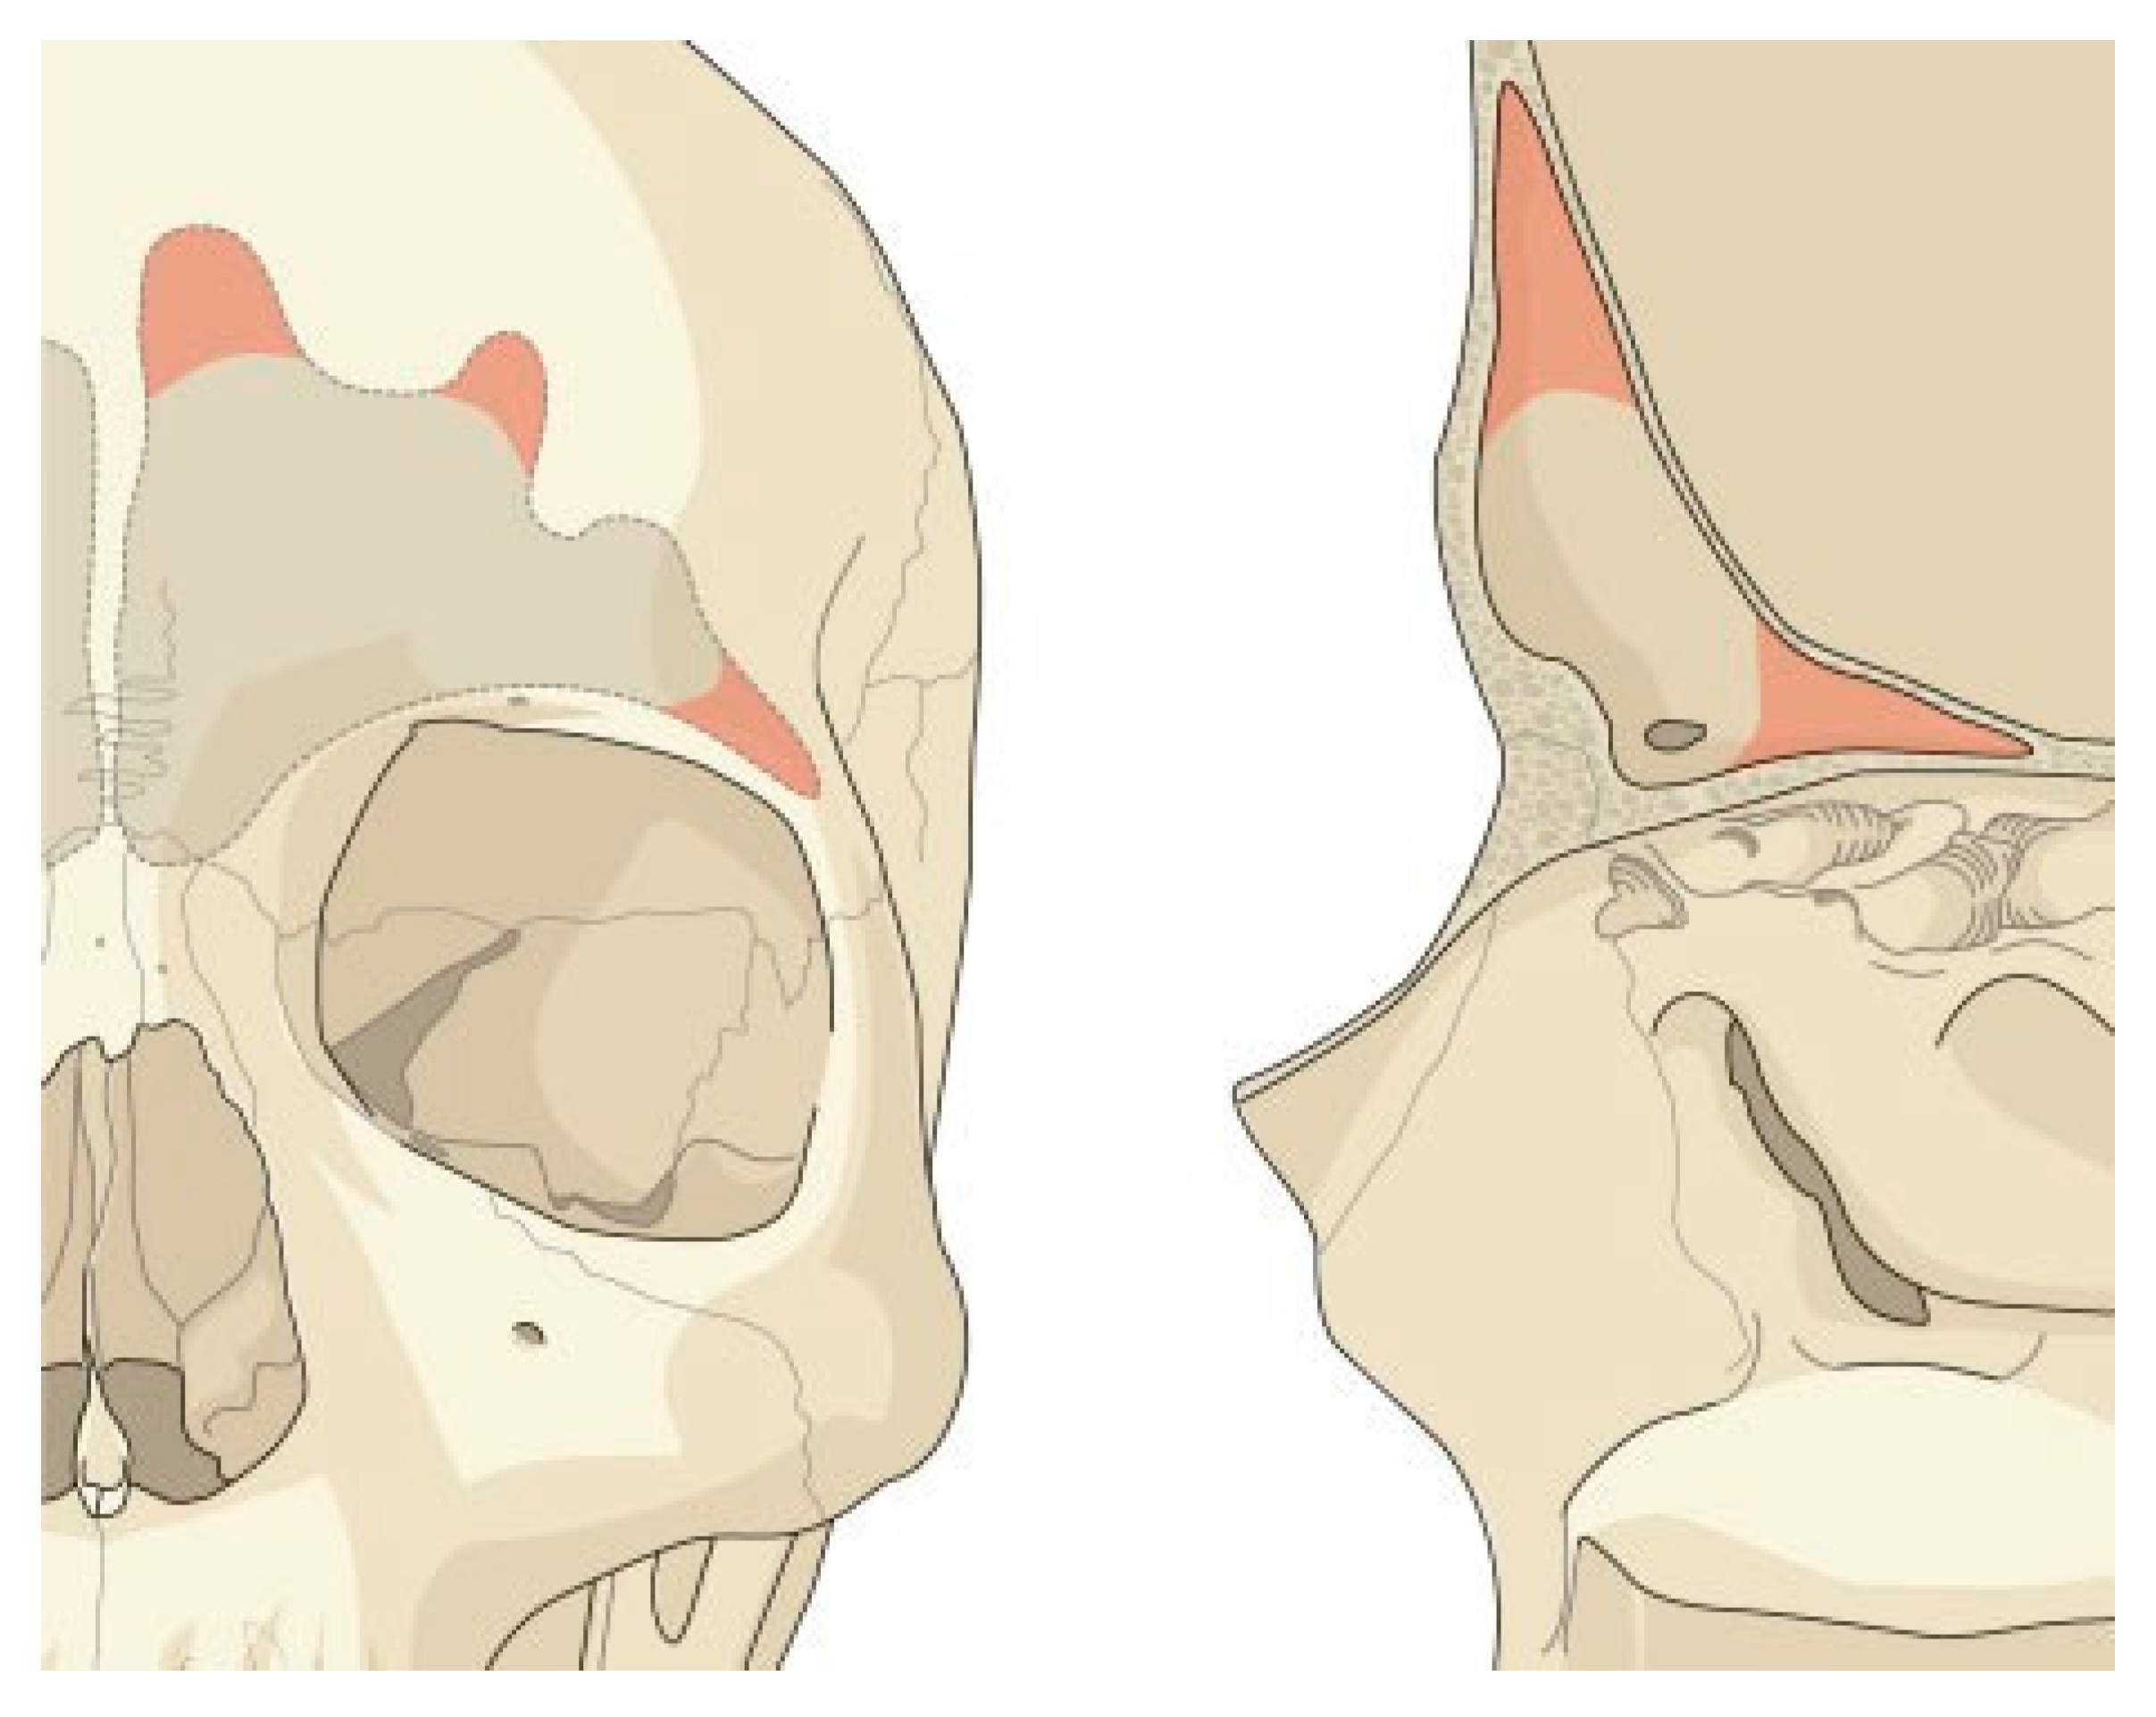

The frontal sinus is absent at birth. At 2 years of age, the anterior ethmoid air cells invade the frontal bone, and by 15 years of age, the frontal sinus is adult size. The floor of the sinus forms the medial portion of the orbital roof. The posterior table forms a portion of the anterior cranial fossa. The anterior table forms part of the fore- head, brow, and glabella (Figure 1A,B). However, the size and shape of the adult frontal sinus is highly variable. The nasofrontal recess is the sole outflow tract for the frontal sinus and is the narrowest point of an hourglass configuration. Each ostium is ~3 × 4 mm in diameter and located posteriorly, inferiorly, and medially on the floor of the sinus [7,8].

Figure 1.

Frontal sinus anatomy. The anterior table of the frontal sinus is thick bone and provides forehead contour. The posterior table is thinner and constitutes a portion of the anterior cranial fossa. The floor of the sinus makes up a portion of the orbital roof. The frontal sinus ostia is located in the medial, posterior, and inferior portion of the sinus floor.